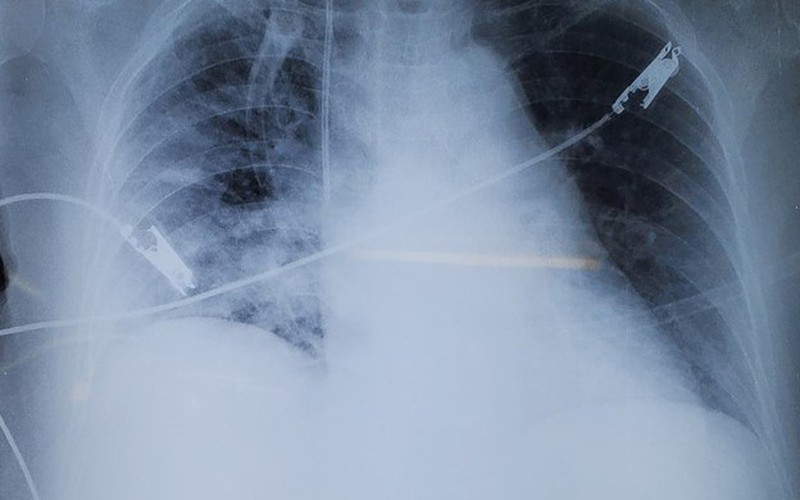

Tại đây, tiên lượng được tình trạng bệnh rất nặng do nhiễm khuẩn huyết, viêm phổi nặng, sốc nhiễm khuẩn kèm bệnh lý nền đái tháo đường, các bác sĩ hồi sức đã nhanh chóng điều trị tích cực cho bệnh nhân. Bệnh nhân được hỗ trợ hô hấp, hồi sức chống sốc bằng bù dịch và vận mạch, theo dõi huyết động xâm nhập, sử dụng kháng sinh sớm và phổ rộng, kiểm soát đường huyết.

Sau 2 ngày hồi sức tích cực, tình trạng lâm sàng được cải thiện, bệnh nhân tỉnh, huyết áp ổn định, giảm khó thở, ăn uống trở lại được và tiếp tục được theo dõi. Sau 10 ngày điều trị, sức khỏe bệnh nhân tiến triển tốt và được xuất viện.